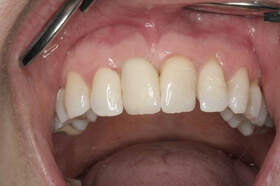

Több, mint tízéves hidak, elkopott fogak. Kezelési terv: a régi hidak cseréje és a többi fog ellátása fém-kerámia koronákkal

Az elkészült fém-kerámia koronák, hidak